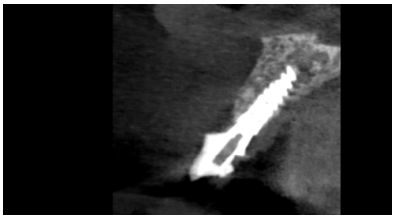

Se llevó a cabo una exploración radiológica que incluyó una radiografía periapical y la realización de un CBCT con el fin de conocer mejor la distribución de la fractura que presentaba el ICSI. (Figura 2). En la exploración radiográfica se confirma la presencia de una fractura oblicua que comprende la región del tercio medio radicular y se extiende en sentido corono-palatino hacia la región coronal. Así mismo, se puede observar la presencia de un tratamiento de conductos dentro de la normalidad y la ausencia de tabla vestibular en la región de los dos tercios coronales de la raíz del ICSI.

explorado en CBCT. Se puede apreciar una fractura cuya extensión compromete la estructura coronal y del primer tercio coronal del incisivo.